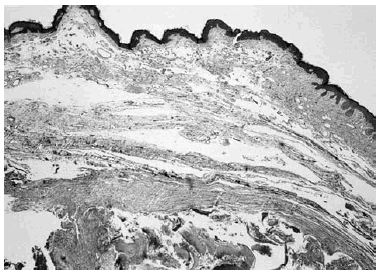

Paciente varón de 22 años, sin antecedentes personales o familiares de interés, que consultó por la presencia de una tumoración, de 9 meses de evolución, en región escapular derecha. En la exploración se observó una lesión excrecente de 3 cm (fig. 1A), para la que, tras el diagnóstico clínico de quiste epidermoide, se propuso la extirpación quirúrgica. El paciente no acudió el día previsto para su intervención y reapareció en la consulta 5 meses más tarde debido al rápido crecimiento de la lesión y a los importantes cambios de la piel que la recubría. En ese momento presentaba una lesión tuberosa de 7 x 5 cm recubierta por una piel atrófica, plegada y de aspecto queloideo (fig. 1B). A la palpación se apreciaba la existencia en profundidad de un nódulo de consistencia dura y de aproximadamente 4 x 3 cm que tras su exéresis demostró histopatológicamente tratarse de un tumor localizado en dermis profunda y tejido subcutáneo, constituido por una serie de lóbulos irregulares agrupados en un gran nódulo rodea-do por una gruesa pseudocápsula; estaba compuesto por dos tipos celulares: células basalioides y gran cantidad de células sombra. En la dermis que recubría el tumor destacaba un edema intenso, con un aumento importante del número de vasos y una vasodilatación muy marcada (fig. 2). Las fibras colágenas se encontraban disminuidas y fragmentadas (fig. 2) y las elásticas estaban prácticamente ausentes como pudo comprobarse con la tinción de orceína.

Fig. 2.--Dermis laxa, edematosa, con dilataciones linfáticas sobre una gruesa pseudocápsula que envuelve los cúmulos de células sombra de un profundo pilomatricoma.